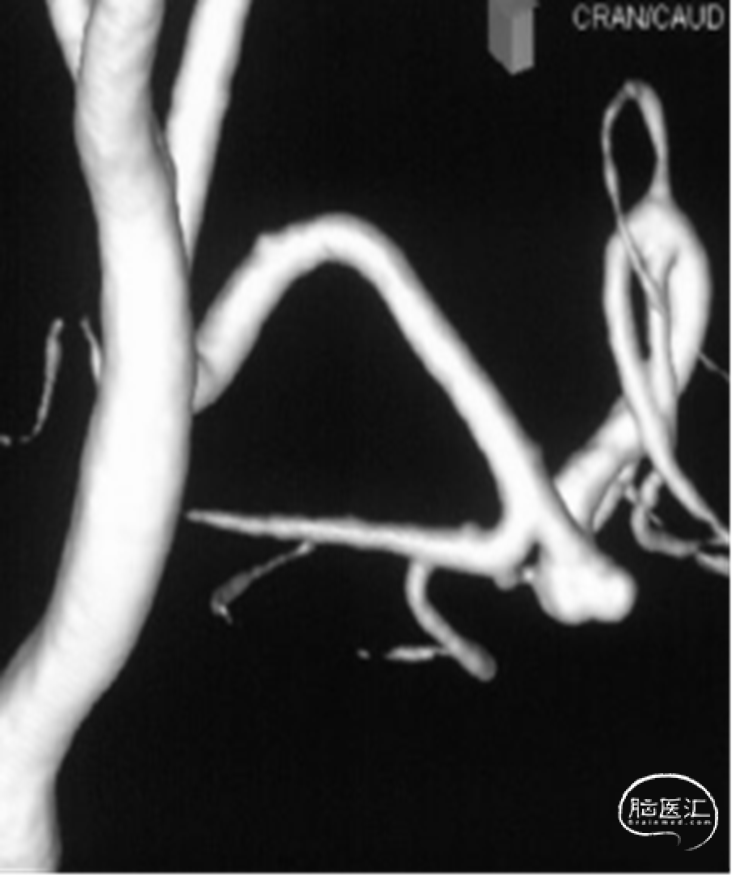

入院急诊DSA提示右侧小脑后下动脉远端动脉瘤,动脉瘤位于PICA蚓部分支

二维及三维重建提示动脉瘤形态不规则,可见瘤壁存在小泡凸起,瘤颈宽3.6mm,瘤高2.0mm,瘤体最大径2.5mm,未见血管明显痉挛